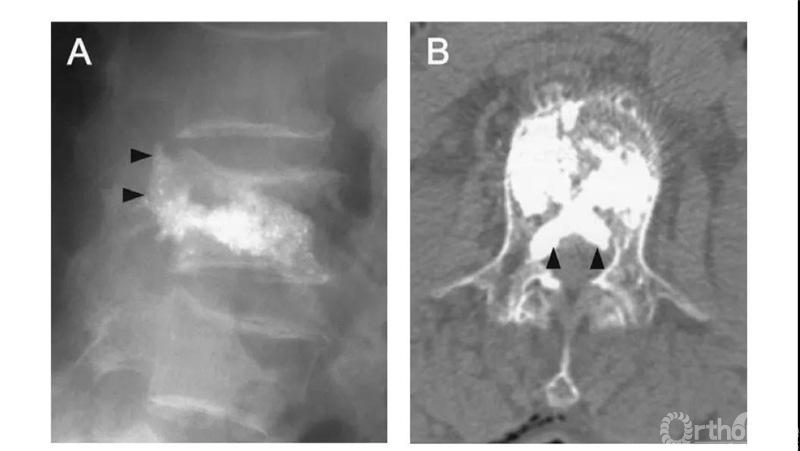

比如这例,侧位X片看骨水泥在椎弓根里,可CT一扫发现已经渗漏进入椎管。

侧位X片看骨水泥在椎体里,CT显示渗漏进入椎管。